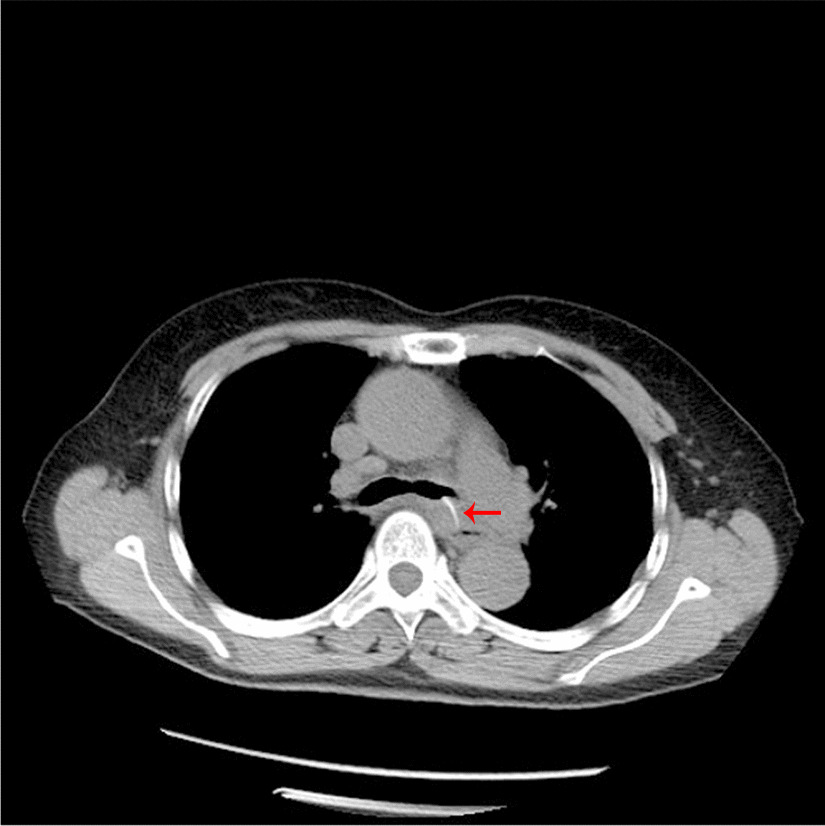

A female patient, 72 years old, was admitted for “retrosternal pain for 4 days during eating” with a healthy history before. Four days ago, the patient had a foreign body sensation in the pharynx after eating freshwater fish. Then she ate as usual but felt retrosternal pain when eating. One day ago, the pain worsened after eating rice cake and was accompanied by severe irritant dry cough without fever, hemoptysis, or hematemesis. The patient was admitted to Regional medical center for National Institute of Respiratory Disease, Sir Run Run Shaw Hospital, School of Medicine, Zhejiang University. Chest plain computed tomography (CT) scan suggested “flat esophagus and bronchial bifurcation with a high-density shadow, a foreign body was considered with the length of 2.8 cm that crossed the left main bronchial wall, and the local bronchial wall mucosa thickened” (Figs. 1, 2). Treatment was supportive with fasting, fluid infusion, monitoring and so on. During the operation, a rigid esophagoscope (S121; Hangzhou Tonglu Medical Optical Instrument Co., Ltd, Zhejiang, China) was used under general anesthesia with endotracheal tube. It was observed that the mucosa ulcer was at the 2 o’clock direction in the esophagus 26 cm away from the incisors, with hyperemia and swelling of the surrounding mucosa. No obvious foreign body was found in the cavity. Under a fiberoptic bronchoscope (BF-260; Olympus Optical Co., Ltd, Tokyo, Japan) via the endotracheal tube, a needle-shaped foreign body (considering fish bone in combination with medical history) in the proximal part and near the entrance of left main bronchus could be seen intraoperatively, and penetrated the bronchial wall. Local bronchial wall showed granulation tissue hyperplasia, mucosal swelling and easy bleeding (Fig. 3). After the granulation tissue was cleaned intraoperatively and the fish bone was exposed, the holmium laser (VersaPulse 80/100 W PowerSuite; Lumenis Ltd, Israel) with the settings of 1 J and 8 Hz was used to broke the fish bone in the middle which was located in the left main bronchus, and foreign body forceps (JHY-FG-18-120-A4; Jiuhong Medical Instrument Co., Ltd. Changzhou, China) were used to remove the two segments, respectively. There was no significant active hemorrhage in the bronchus after operation (Fig. 4). The entire operation under the fiberoptic bronchoscope lasted for 20 min. The foreign body was a sharp and hard fish bone about 3 cm in length (Fig. 5). A jejunal nutrition tube was indwelling during the operation, and nasal-feeding nutrition as well as gastrointestinal decompression were given postoperatively. Secondary infection and leakage were also monitored. No obvious leakage was noted in upper gastrointestinal contrast half a month after the operation. Then, the jejunal nutrition tube was removed, and there was no obvious discomfort when having semi-fluid food through the mouth.

Fig. 1.

Plain axial CT scan of the chest. The chest CT image shows that a slender fish bone crosses the esophageal wall and considered involves the left main bronchial wall